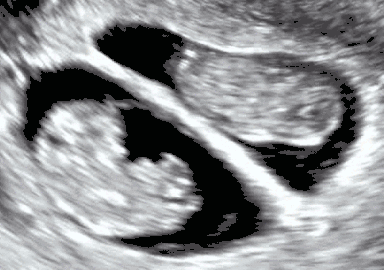

Echogenicity (sometimes as echogenecity) or echogeneity is the ability to bounce an echo, e.g. return the signal in medical ultrasound examinations. In other words, echogenicity is higher when the surface bouncing the sound echo reflects increased sound waves. Tissues that have higher echogenicity are called "hyperechoic" and are usually represented with lighter colors on images in medical ultrasonography. In contrast, tissues with lower echogenicity are called "hypoechoic" and are usually represented with darker colors. Areas that lack echogenicity are called "anechoic" and are usually displayed as completely dark.[1]